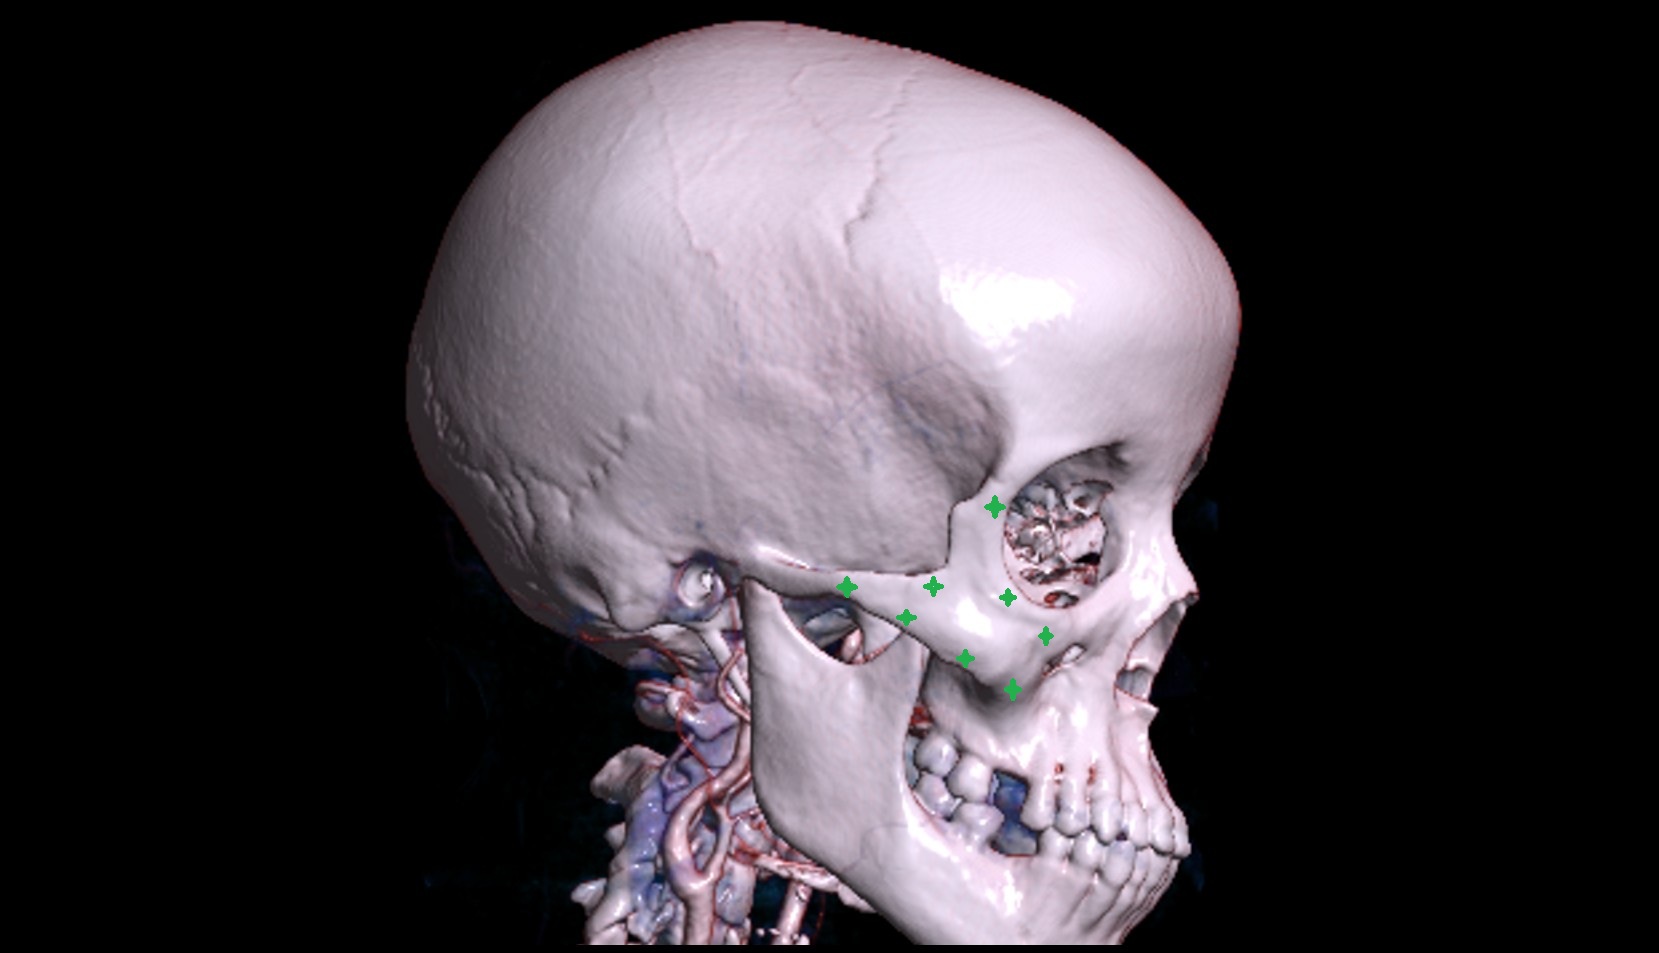

- Temporomandibular joint

- Mandibular condyle

- Mandibular fossa

- Zygomatic arch

- Zygomatic bone